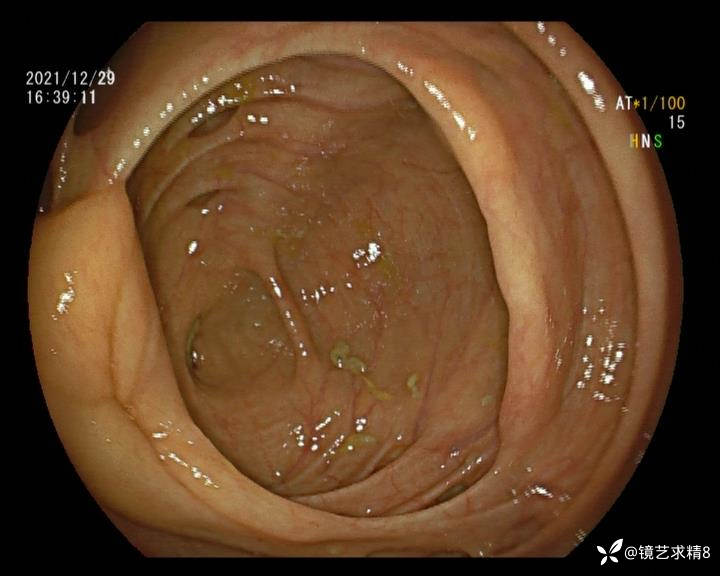

结肠内违建⥤结肠多发憩室☞续

患者以消化道出血入院,胃镜未见异常,肠镜进入乙状结肠就看到很多憩室,同时还看到肠腔用清肠药后移动下来1枚尖锐的枣核,这么多憩室,这个枣核扎入憩室的机会非常大,推测应该是掉入一坑🕳就算出来还会有很多坑🕳🕳🕳等着,掉入憩室内很容易刺破血管,这可能就是消化道出血的原因,继续前进可以看到有一些憩室内翻,还有一些息肉,问题来了,那么多憩室,犯罪分子是抓住了,它在那些憩室内作过案?到达回盲部后挨个冲洗,但憩室大小又不足以把镜头进入憩室内观察,针对有血块的憩室冲洗后可疑出血的以夹子闭合或套扎,取出枣核,如果有锥形透明帽可能钻入憩室精准电凝效果更好,若内镜下操作失败介入治疗成功率更高,经内镜下治疗后观察未再出血出院。

目前研究认为,憩室出血与憩室内血管分布及走行有关。位于憩室颈部或基底部的局部动脉血管仅靠黏膜层与肠腔相隔,随着动脉本身退化或机械损伤,可破裂进入肠腔。值得注意的是,憩室出血通常与炎症无关,憩室炎很少发生明显的出血。